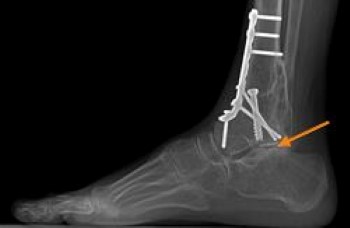

Hindfoot (Heel Region of the Foot)

A fusion of the affected joints of the hindfoot is the most common surgery used to treat patients with flatfoot or arthritis of the hindfoot.

- A triple arthrodesis is a fusion that involves all three joints in the back of the foot.

- Occasionally, the joint on the outside of the foot is not fused if there is little to no involvement of that joint (this is at the surgeon's discretion). This type of fusion eliminates the side-to-side motion of the foot, while preserving most of the up and down movement.

- If RA is only in one joint, a fusion of just that affected joint may be all that is needed.

Any fusion of the hindfoot will limit side-to-side motion of the foot. This will affect walking on uneven ground, grass, or gravel. There is no method to replace the joints of the hindfoot.